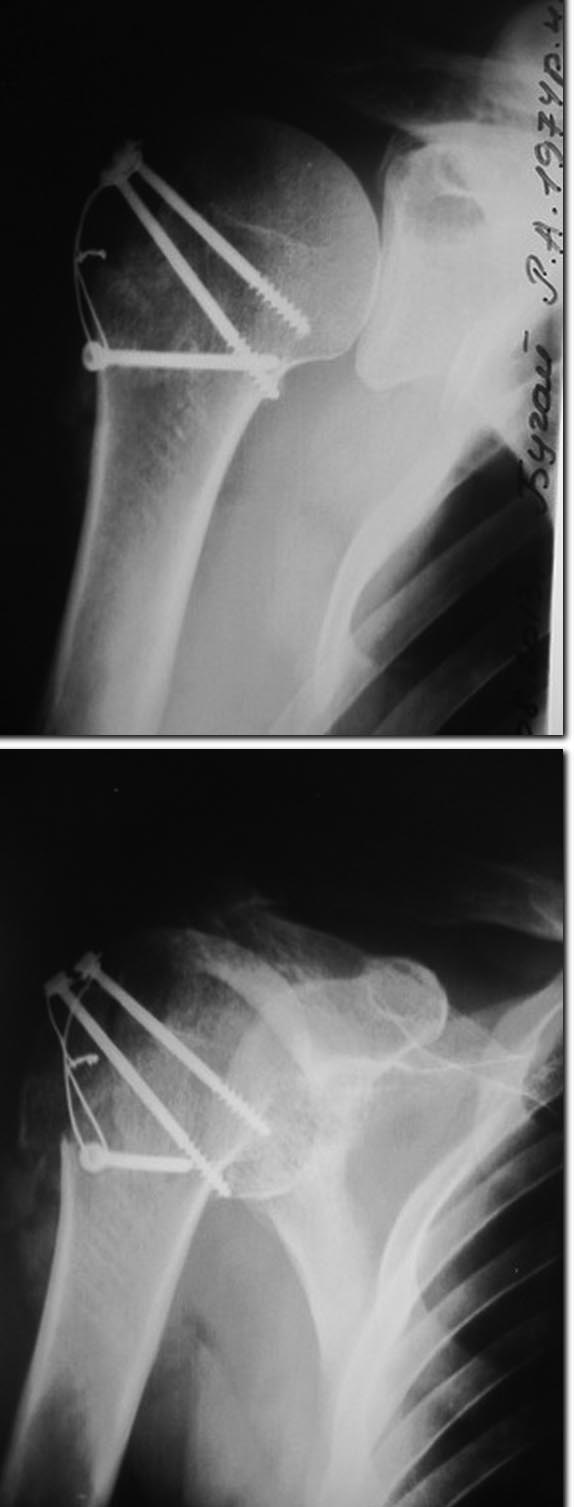

Добрый день! Прооперировали пациента, передне-дельтовидным доступом, в

рубцовых тканях с техническими трудностями(прошло~2 месяца с момента

травмы) выделили сместившийся большой бугорок. Подтянули его(на сколько

вышло возможным технически), фиксировали 2 спонгиозными винтами(отломок

достаточно большой оказался), после чего для большей стабильности -МОС

по Веберу. Иммобилизация 3 недели косыночной повязкой, после чего

планируется разработка движений в плечевом суставе. На контрольных

снимках(прилагаются) остаточное смещение бугорка есть, но

интраоперационно при отведении руки- импиджмент-синдрома не

наблюдалось(бугорок фиксирован, смещения кверху бугорка не происходит,

как до операции).Всем докторам огромное спасибо за советы и правильно

выбранную тактику лечения!